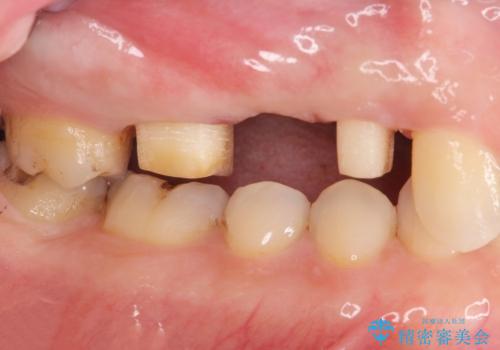

- 昨晩より歯が痛む、痛みをとって欲しいと希望され来院されました。

検査をしたところ、右上小臼歯に破折が見られ保存が難しい状況です。

抜歯を行い、咬合機能の回復を行いますが、咬合関係や非常に強い噛み合わせの問題をふまえ、咬合面をメタルにしたメタルボンドブリッジで治療を行うこととしました。